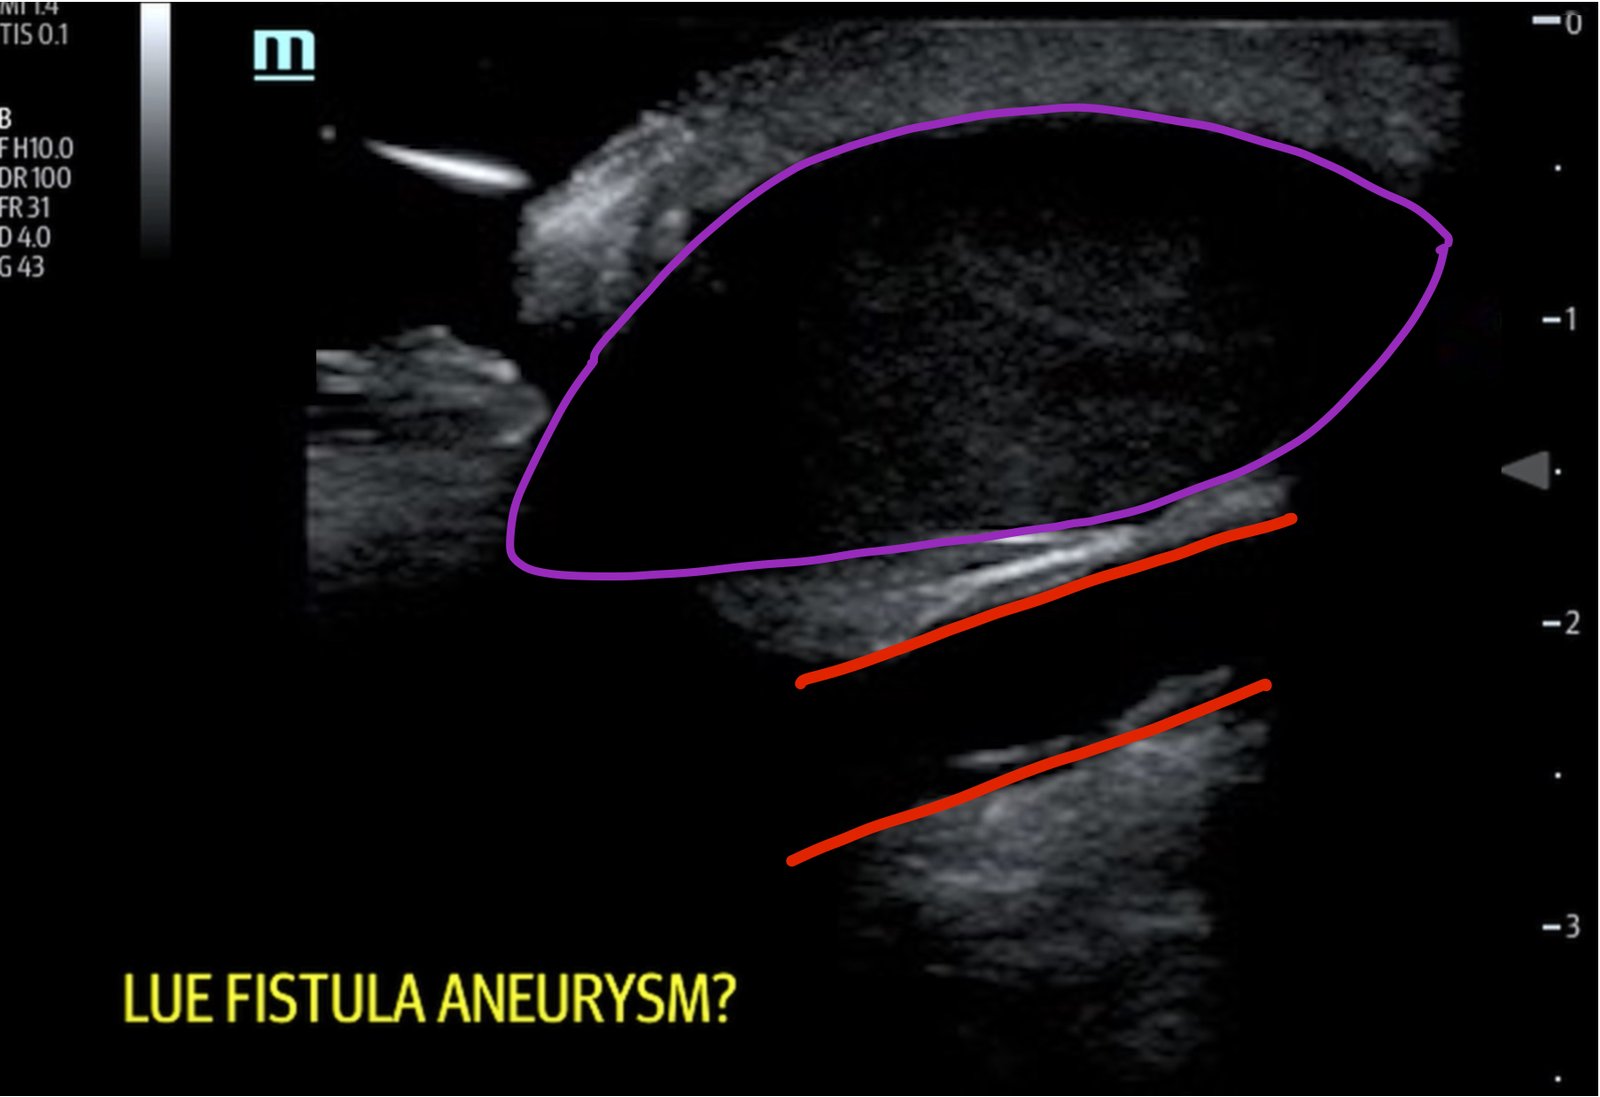

A bedside ultrasound of the mass demonstrated a large compressible hypoechoic structure (see purple outline) above the arteriovenous graft (see red outline). The contents demonstrated movement of fluid within the structure. This was confirmed with Doppler mode, which allowed for visualization of flow communicating between the structure and the underlying vessel, which is diagnostic for a pseudoaneurysm.

Pseudoaneurysms are a relatively rare complication of vascular access with an incidence of 2%-10%.3 They often result from weakening of the vessel wall secondary to inflammation from infection or chronic needling which leads to scarring.4 Concerning signs that warrant vascular surgery consultation include an aneurysm that is symptomatic, twice the size of the graft, expanding, threatened viability of overlying skin, or large/multiple aneurysms limiting number of cannulation sites.5 Doppler ultrasound is the principal means of diagnosis with a sensitivity of 94%.6 On ultrasound there are several characteristic findings that can alert the provider to the diagnosis of pseudoaneurysm. On color doppler, visualization of a communication between the vessel and fluid collection external to the vessel is diagnostic.7 This connection is classically described as the yin-yang sign.7 Spectral doppler can demonstrate biphasic flow through the communication.7